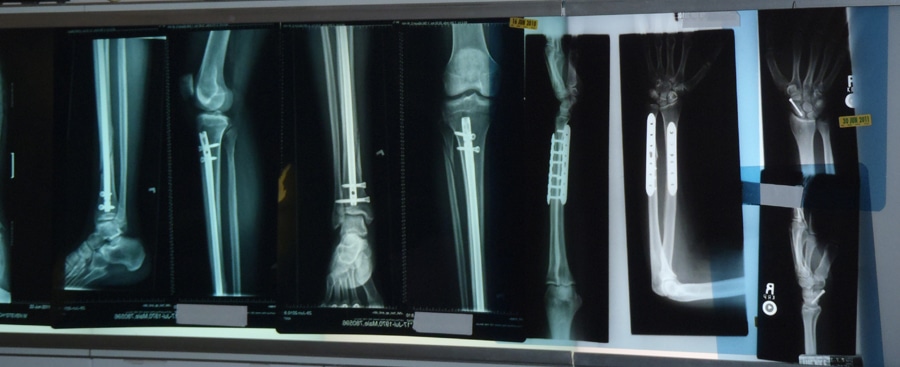

In some instances, you’ll immediately hear a sudden snap after getting injured. Pain will quickly begin to set in. You may also notice that one of your limbs looks deformed. A doctor will be able to determine the extent of the fracture. Getting an X-ray is by far the most popular method to diagnose a fracture. If the fracture isn’t detected using an X-ray, MRIs and CAT scans may be necessary.